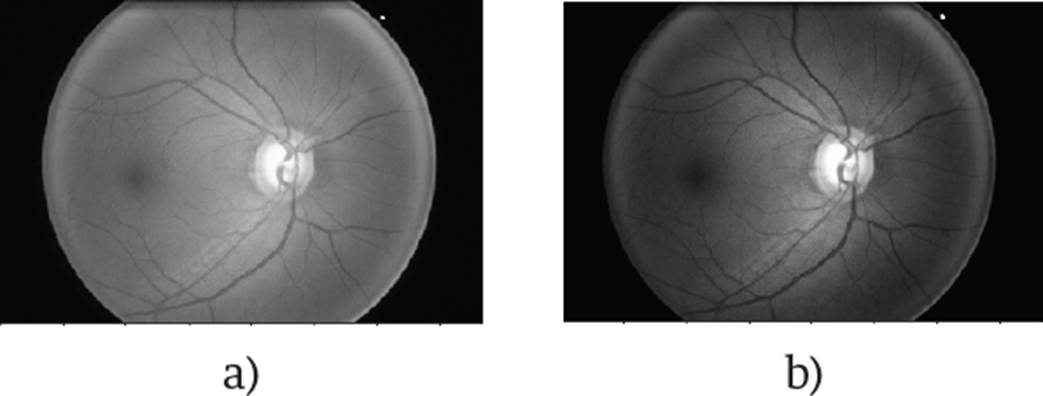

Figure 1 shows an image of the fundus in a healthy condition where the most important parts can be seen, such as the optic nerve, which is where the study of this work will be focused. The outer part of the optic nerve is called the optic disk (OD), and the smaller blurry inner circle is called the optic cup (OC). In the OD area, we can see the main arteries and veins, whereas the veins have a darker color than the arteries. Veins usually are larger in caliber than arteries, having an average AVR ratio of 2:3 [17].

Figure 1 Image of the optic nerve [16]